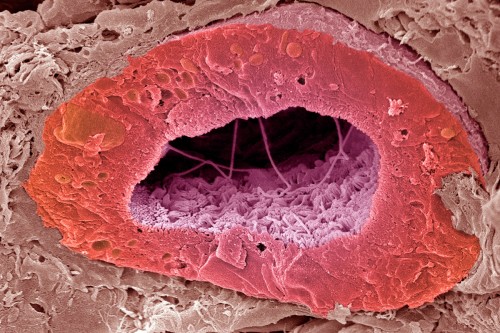

Our researchers have pioneered the use of imaging methods such as PET/CT, MRI, and live microscopy to observe and measure biological processes over time. By highlighting living cells or tissues with specific agents, we use these technologies to aid laboratory investigations into the root causes of cancer and to develop innovative approaches to improve diagnosis and treatment.